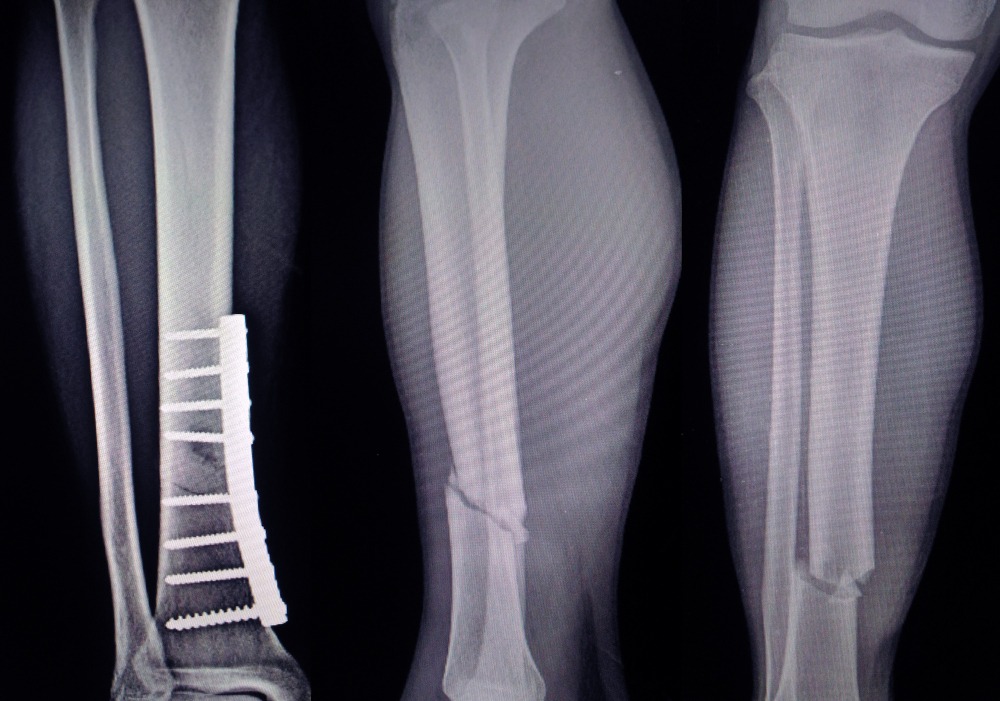

Bone Deformity Correction Surgery in Pimpri Chinchwad – Restoring Proper Bone Alignment and Function